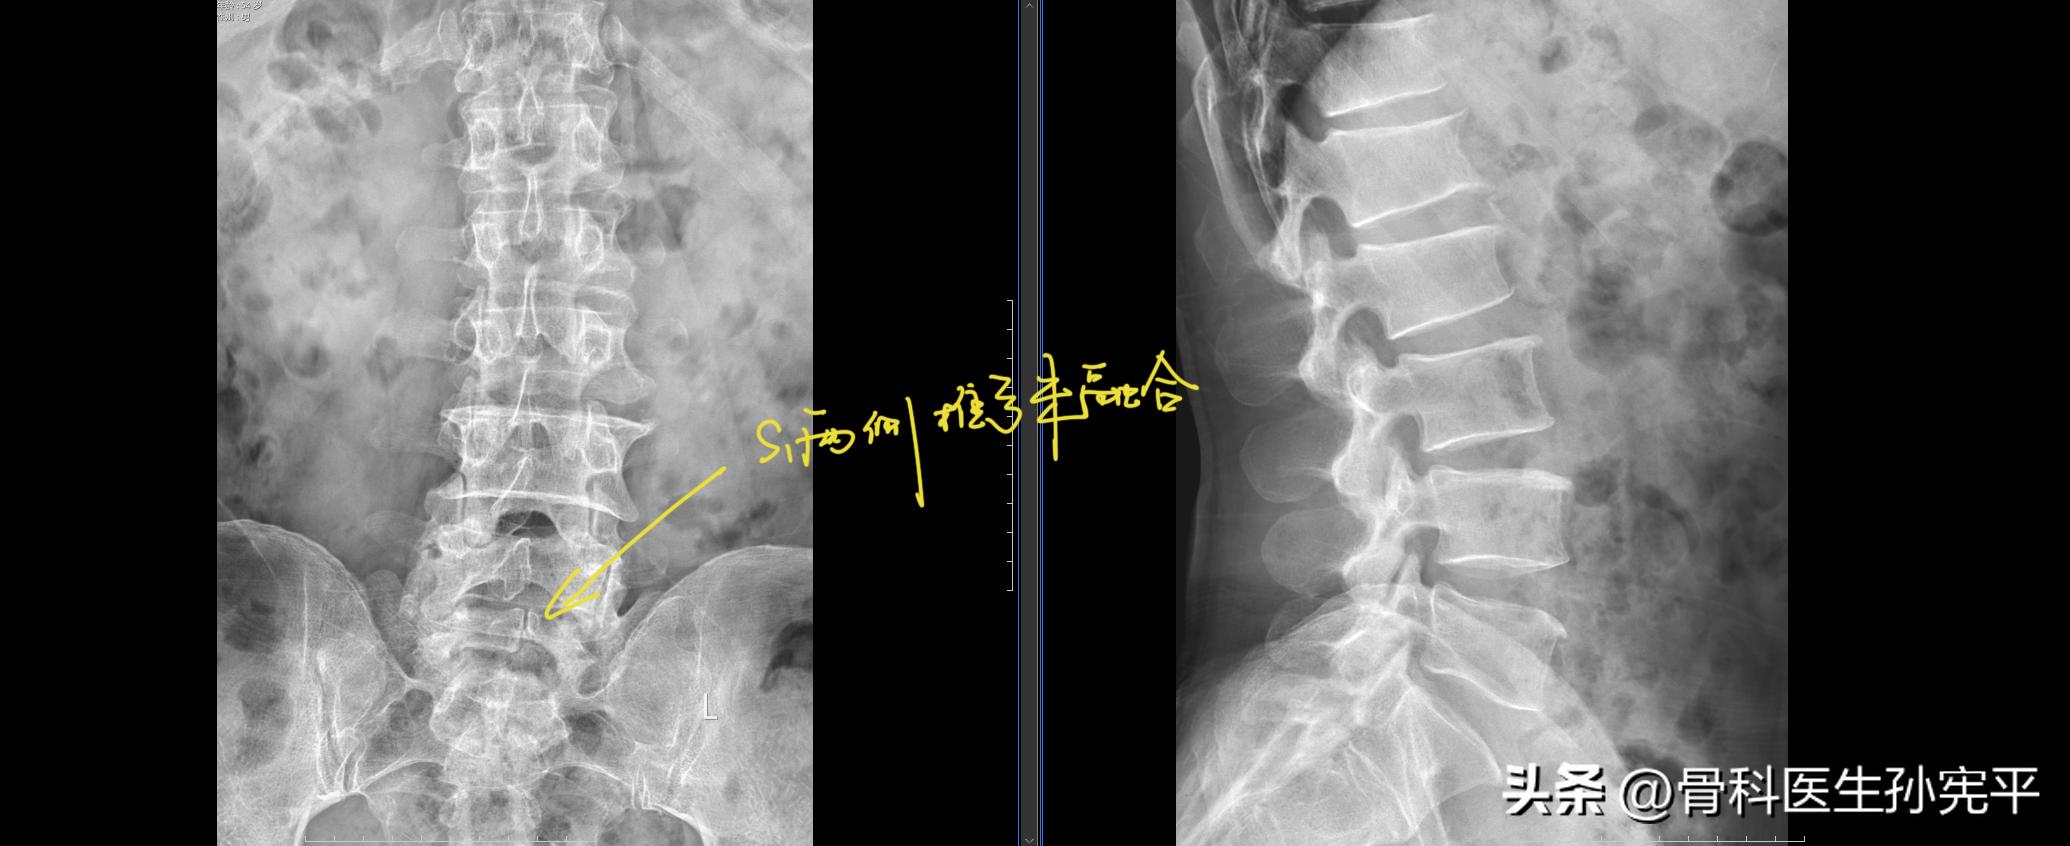

病例2:反复腰痛2年。

骶1隐性脊柱裂

阅片见骶1隐形脊柱裂,腰椎轻度侧弯,椎体增生退变,骶1两侧椎弓未融合,形成纵行透亮线,为发育异常。